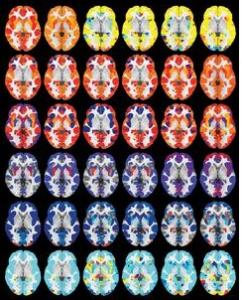

Les chercheurs ont évalué via IRM le cerveau de 1.189 jeunes âgés de 8 à 23 ans, ont relevé de multiples mesures de la matière grise dont le volume, la densité et l'épaisseur corticale. La neuro-imagerie a également permis aux chercheurs de relever plusieurs mesures de la structure du cerveau, de manière non invasive. L'analyse de toutes ces données a permis aux scientifiques de caractériser la façon dont le cerveau d'un enfant diffère de celui d'un adulte et dont le cerveau d'une jeune femme diffère de celui d'un jeune homme.

21 April, 2017 10.1523/JNEUROSCI.3550-16.2017 Age-related effects and sex differences in gray matter density, volume, mass, and cortical thickness from childhood to young adulthood (Visuel@Penn Médicine)